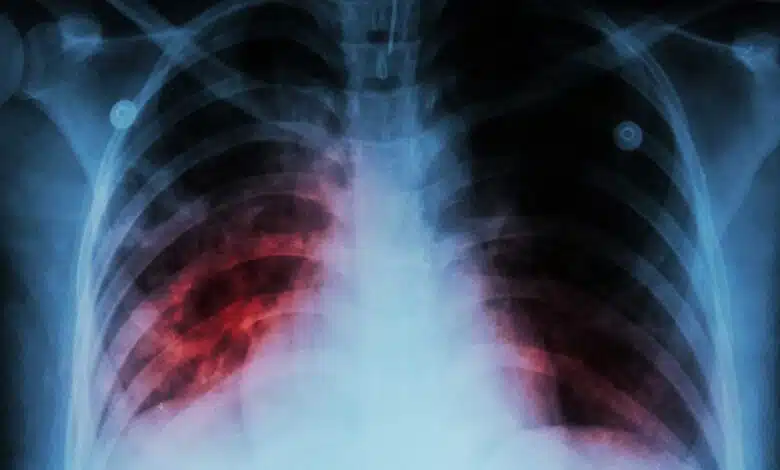

भारतीय चिकित्सा अनुसंधान परिषद (ICMR) के महानिदेशक डॉ. राजीव बहल ने सार्वजनिक स्वास्थ्य में नई परियोजनाओं और उपलब्धियों के बारे में बात की और तपेदिक (TB) के निदान में एक महत्वपूर्ण प्रगति पर प्रकाश डाला: TB की जांच के लिए एक नया हाथ से पकड़े जाने वाला एक्स-रे उपकरण विकसित किया गया है, जो प्रारंभिक पहचान और उपचार प्रयासों को बढ़ाता है, अंततः सार्वजनिक स्वास्थ्य परिणामों में सुधार करता है।

बुधवार को ड्रग रेगुलेटरी अथॉरिटीज (ICDRA) इंडिया-2024 के 19वें अंतर्राष्ट्रीय सम्मेलन में बोलते हुए, ICMR के महानिदेशक डॉ. बहल ने कहा, “हाथ से पकड़े जाने वाले एक्स-रे बहुत अधिक कीमत पर उपलब्ध हैं और अब IIT कानपुर ने ICMR के साथ साझेदारी में स्वदेशी रूप से एक हाथ से पकड़े जाने वाला एक्स-रे विकसित किया है, जिसकी कीमत आयातित हाथ से पकड़े जाने वाले एक्स-रे की लागत से आधी से भी कम होगी। इससे यह सुनिश्चित होगा कि हम रोगियों और यहां तक कि कमजोर आबादी के घरों के पास TB की जांच कर सकें।”